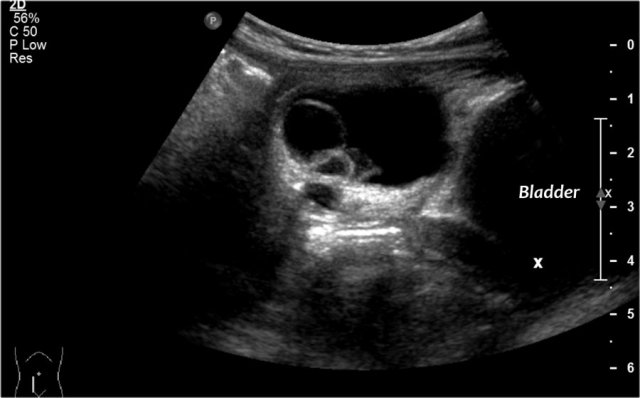

Two-year-old girl with a sacral mass. On ultrasound a cystic lesion anterior to the sacrum is seen, compatible with a class 4 sacrococcygeal teratoma. It was completely resected.

The intraspinal extension was visible on ultrasound, but MRI provides a better overview and a document for future comparison.

A parasagittal MRI shows a presacral cystic mass.